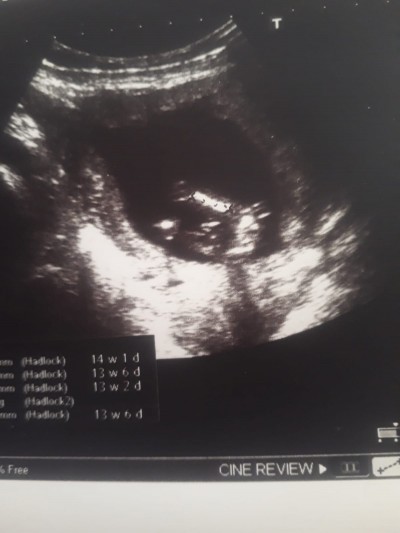

Doktora gittiğimde 13+4gunluktu şuan ise 14+3 gunluk

Bacak arası ve erkek duruyor. Kordon değilse tabi doktprlar bu görüntüye erkek diyor